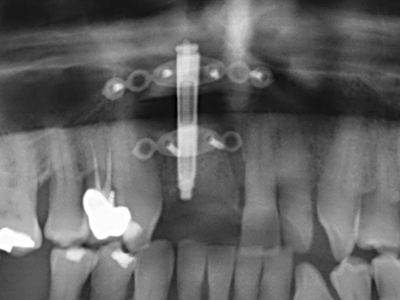

El tejido óseo no solo tiene un contenido puramente mineral, sino que también presenta una importante proporción de fibras de colágeno. Esto no solo garantiza una buena resistencia a la presión, sino también una cierta flexibilidad, que puede aprovecharse para la realización de aumentos. En la plastia de expansión clásica a efectos de una partición ósea, la cresta maxilar atrofiada se divide en su eje longitudinal y, tras alcanzar una profundidad de osteotomía suficiente, se extiende con cuidado (fig. 13-16), en un caso ideal sin desperiostizar de forma visible el maxilar (Brugnami, Caiazzo et al. 2014, Stricker, Fleiner et al. 2014). Los sistemas de tornillos y placas con distancia de expansión creciente han demostrado su eficacia para distanciar entre sí las dos tablas óseas por debajo del umbral de rotura. Por regla general, se requieren anchuras de hueso residual de al menos 3 a 4 mm (Chiapasco, Zaniboni et al. 2006) para garantizar una flexibilidad y una cobertura ósea suficientes de los implantes que van a incorporarse. En caso necesario, una osteotomía de descarga vertical unilateral o bilateral puede mejorar la flexibilidad. Como alternativa a la técnica clásica se ha descrito una combinación con otras técnicas de aumento, sobre todo en la parte bucal.

Con el uso de sierras piezoeléctricas la división se efectúa de forma especialmente cuidadosa y sin pérdidas importantes de las dimensiones, por lo que no se han encontrado diferencias significativas entre los implantes realizados en el maxilar dividido y en la cresta alveolar no deficitaria (Chiapasco, Zaniboni et al. 2006, Danza, Guidi et al. 2009). No obstante, precisamente en la partición profunda y limitada de forma local, es preciso asegurarse de que exista una adecuada irrigación por agua para evitar que se produzcan sobrecargas térmicas en las áreas de osteotomía apical.